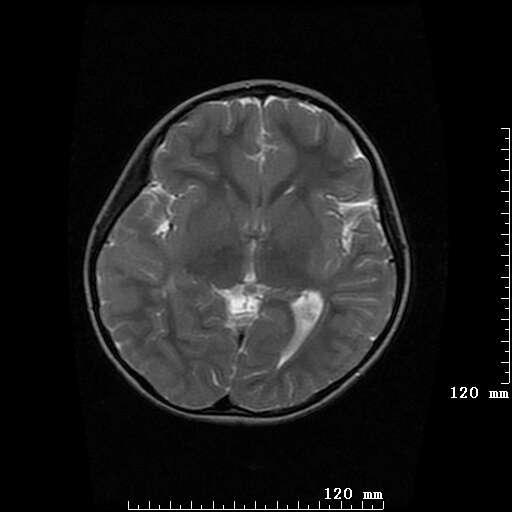

女,7岁,三岁才说话、走路。现智力尚可,走路不稳。临床怀疑大脑发育不全。

脑折质变薄,双侧侧脑室稍扩张,支持考虑脑折质发育不良

侧脑室周围白质软化症。

考虑胼胝体发育不全,髓鞘形成不良。

支持考虑胼胝体发育不全,髓鞘形成不良。

脑裂畸形伴灰质异位

侧脑室周围白质数量减少,侧脑室不对称性扩大,左侧侧脑室后角呈方形改变,脑沟加深,结合临床考虑脑室周围白质软化症(pvl)。期待结果!

只看出灰质异位

支持脑白质发育不良。